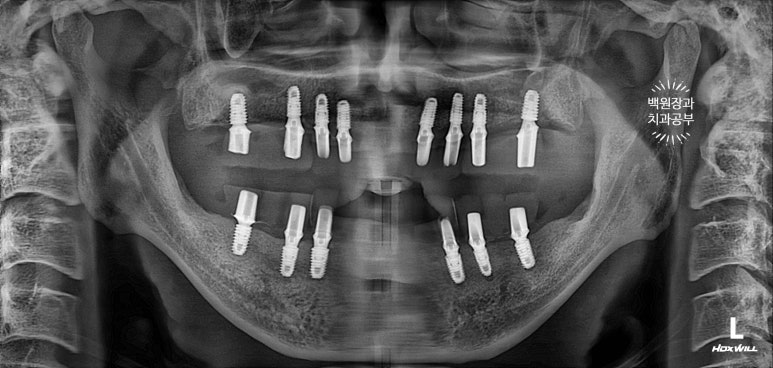

수술 후 촬영한 치과용 파노라마 사진에서 꽤나 예쁘게 심어진 임플란트를 확인할 수 있었습니다.

이렇게 위에는 8개의 임플란트가, 아래에는 6개의 임플란트가 예쁘게 식립된 것을 보실 수 있을겁니다.

마취하고 수술 하는 것은 이렇게 마무리가 됩니다.

깔끔하게 완성된 보철물은 치과용 파노라마 사진에서 확인하실 수 있고,

비전공자가 보아도 나란히 가지런한 임플란트는 편안함을 줍니다.

똑같아 보일 수 있으시겠지만, 6개월이 지난 후 치과용 파노라마 사진입니다.

보통 임플란트의 초기 실패는 6개월 정도 안에 발견할 수 있기에, 이 시기에 한 번 더 오셔서 체크해보는 것이 중요합니다.